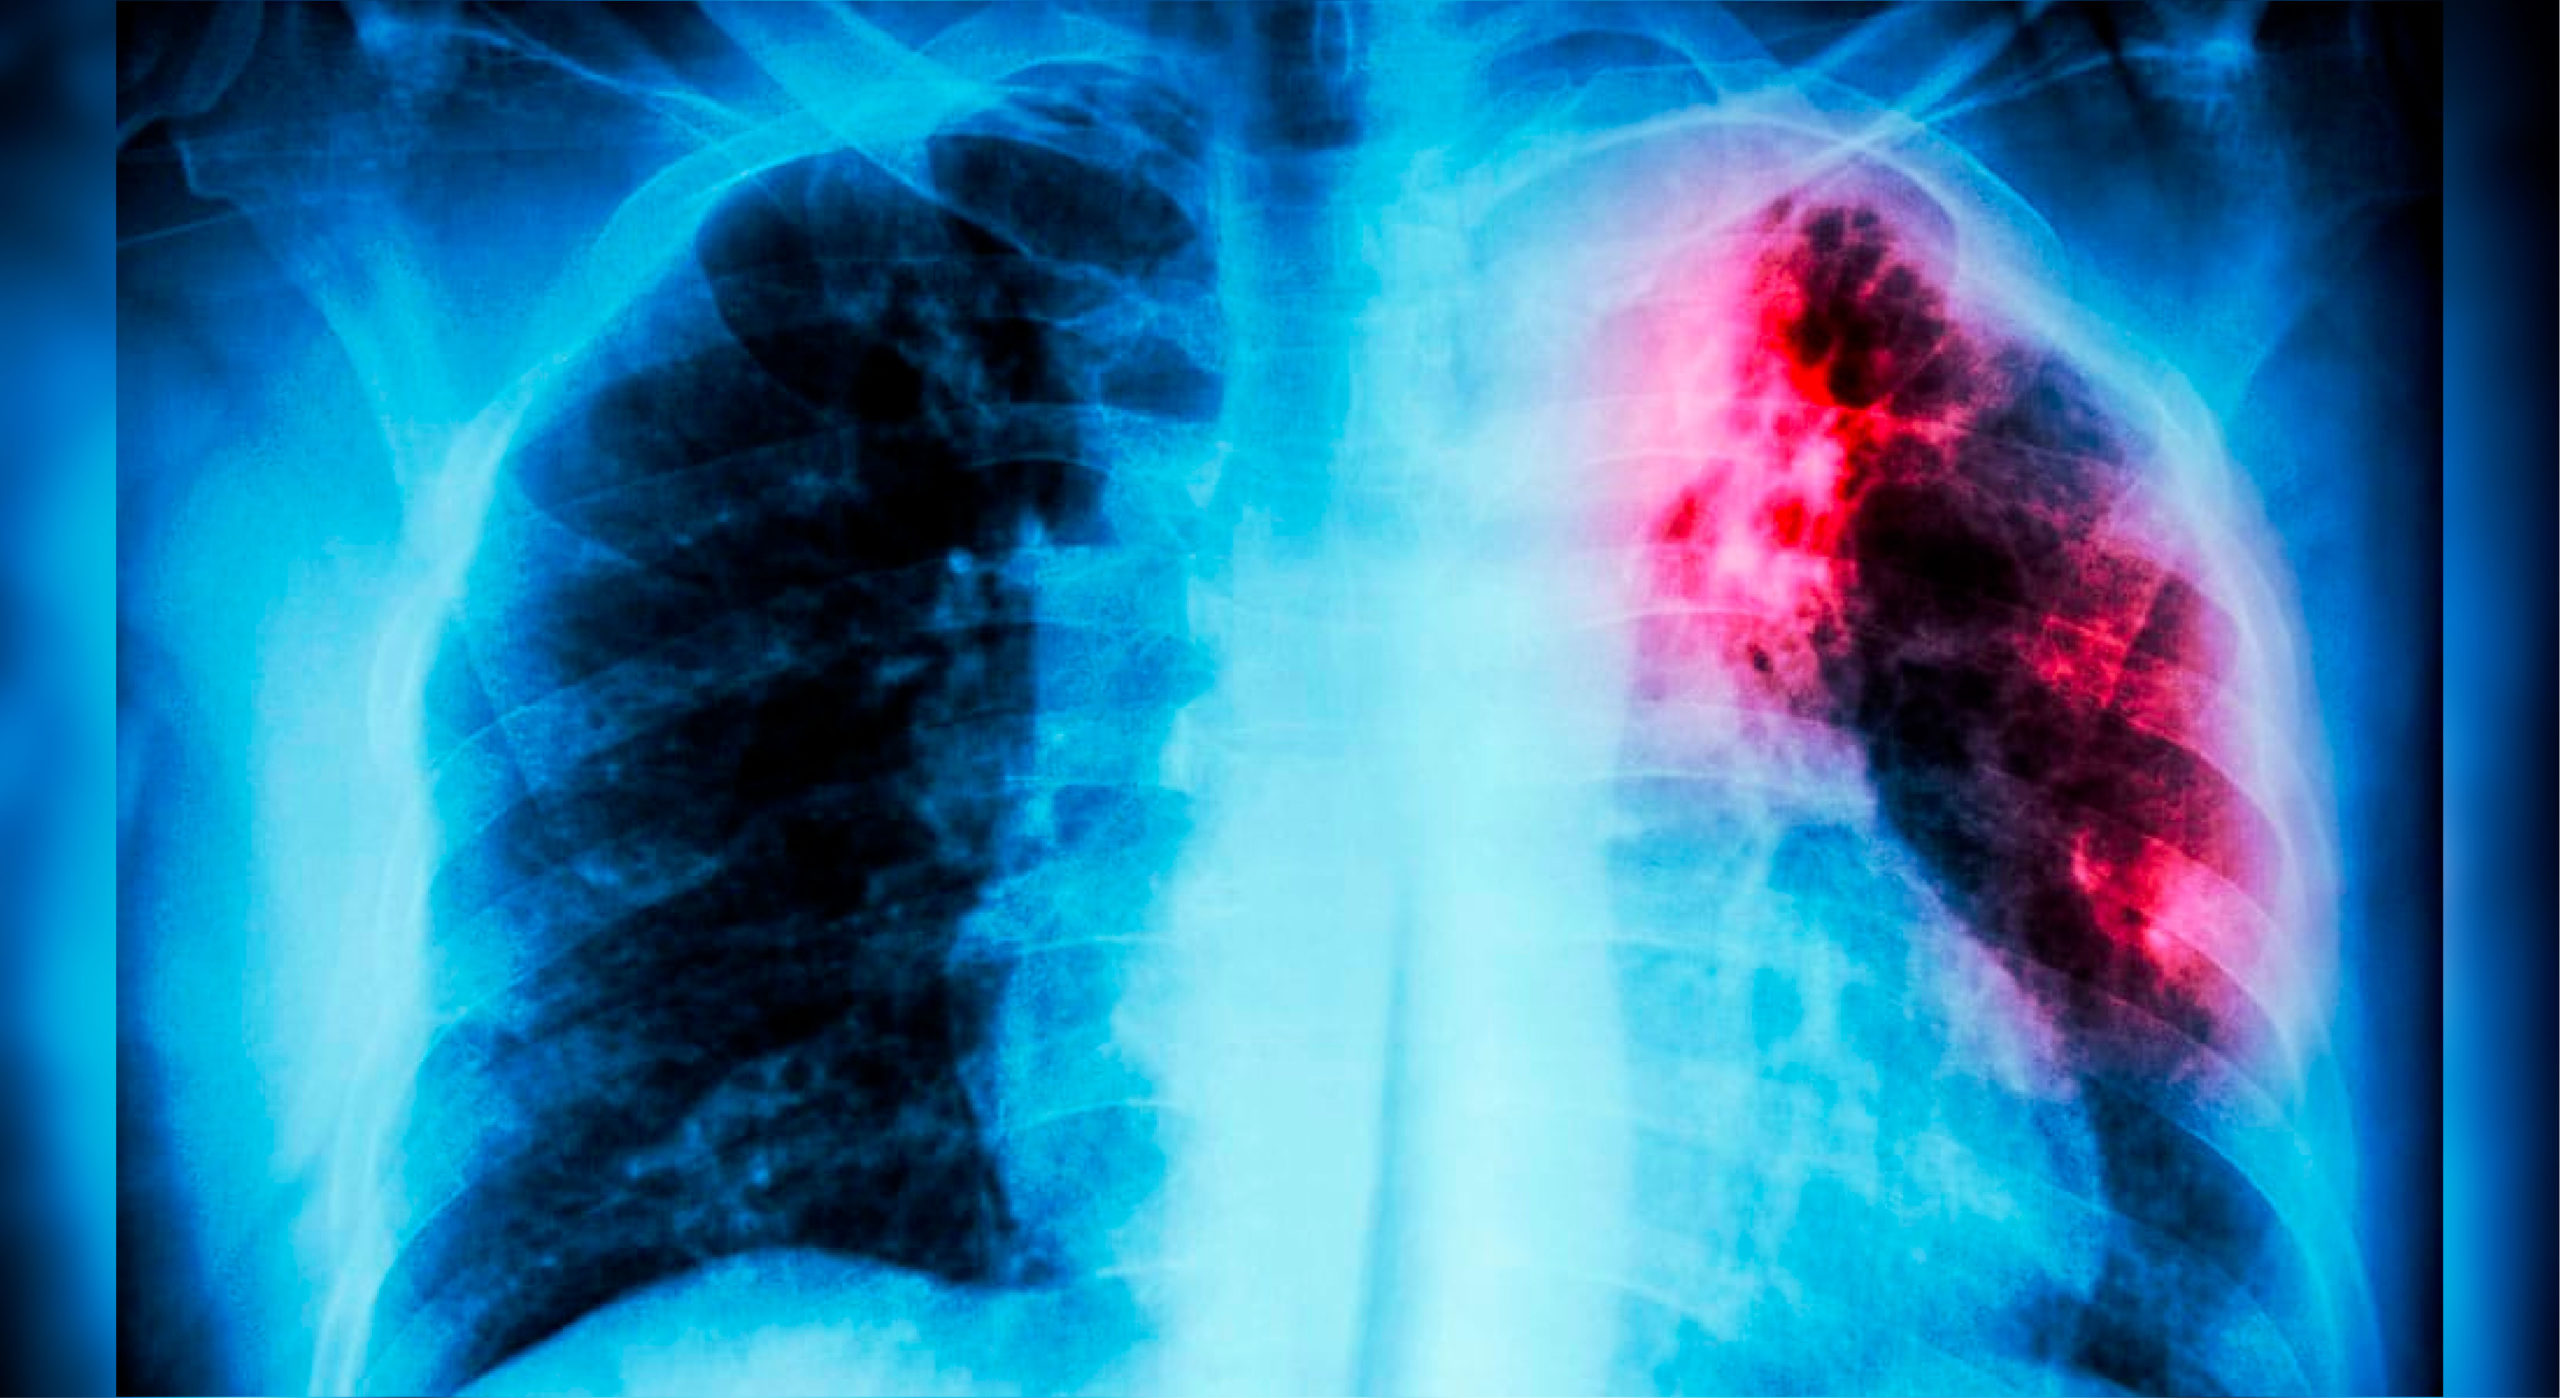

La tuberculosis o TB es causada por una bacteria llamada mycobacterium tuberculosis. Estas bacterias por lo general atacan a los pulmones, pero también pueden atacar otras partes del cuerpo como los riñones, la columna vertebral y el cerebro, en un proceso conocido como tuberculosis extrapulmonar. No todas las personas infectadas por las bacterias se enferman, sin embargo, existen dos afecciones relacionadas con la tuberculosis: la latente y la activa. En cualquiera de los dos casos, si no se trata adecuadamente, la enfermedad puede ser mortal.

La TB se detecta a través de pruebas de laboratorio, radiografía y valoración clínica. Siempre se debe realizar una correlación con los síntomas del paciente, así como el historial de contacto con algún caso de tuberculosis.